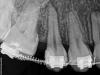

mdkvrn Опубликовано 14 апреля, 2011 Поделиться Опубликовано 14 апреля, 2011 А я думаю что зуб ранее лечился по поводу глубокого кариеса с леч. подкладкой и произошел отрыв пломбы, на снимке есть щель между пломбой и зубом, и заместительный дентин есть, или мне это видится все... Ссылка на комментарий

IRGL Опубликовано 14 апреля, 2011 Поделиться Опубликовано 14 апреля, 2011 на снимке есть щель между пломбой и зубом, и заместительный дентин есть, или мне это видится все...и вторичный кариес тоже. не кажется Ссылка на комментарий

BORA Опубликовано 14 апреля, 2011 Автор Поделиться Опубликовано 14 апреля, 2011 А я думаю что зуб ранее лечился по поводу глубокого кариеса с леч. подкладкой и произошел отрыв пломбы, на снимке есть щель между пломбой и зубом, и заместительный дентин есть, или мне это видится все... щель имеется..есть конечно подозрения что отрыв...но нет чувствительности...и возможно что щель-слабоконтрастная прокладка какая то(флоу какой-нибудь) Ссылка на комментарий

BORA Опубликовано 14 апреля, 2011 Автор Поделиться Опубликовано 14 апреля, 2011 и вторичный кариес тоже. не кажется на апроксималках? Я бы попробовал снять пломбу и посмотреть что дальше будет... не слишком контрастный для заместительного дентина? Ссылка на комментарий

mdkvrn Опубликовано 14 апреля, 2011 Поделиться Опубликовано 14 апреля, 2011 не слишком контрастный для заместительного дентина?сам уже понял что вряд ли, ну подкладка тогда.. Ссылка на комментарий

DokDent Опубликовано 15 апреля, 2011 Поделиться Опубликовано 15 апреля, 2011 щель имеется..есть конечно подозрения что отрыв...но нет чувствительности...и возможно что щель-слабоконтрастная прокладка какая то(флоу какой-нибудь)Если это отрыв,то при такой щели пломба должна быть подвижна Ссылка на комментарий